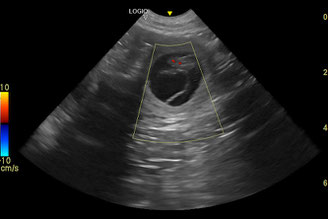

Weil der erste Trächtigkeitsschall nicht ganz so aufschlussreich war wie gewohnt, habe ich nach ein paar Tagen einen weiteren Schall machen lassen. Dieser war dann sehr aufschlussreich, aber weniger erfreulich: Im linken Gebärmutterhorn hat Minna Verwachsungen entwickelt, die bei der Vorsorge vor der Läufigkeit nicht zu sehen waren. In diesem Milieu waren keine eingenisteten Früchte zu finden. Im anderen Horn fanden wir hingegen 2 sehr gut entwickelte Fruchtanlagen. Wir hofften, dass die beiden Zwerge sich weiter so gut machen würden.